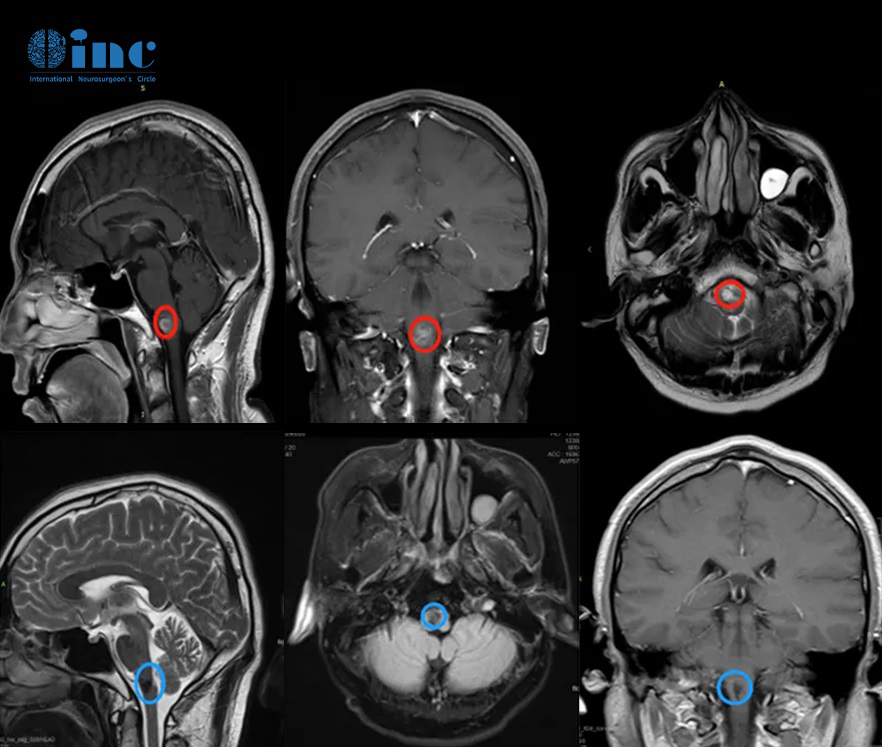

案例1:腦干彌漫內(nèi)生型橋腦膠質(zhì)瘤DIPG

18歲的小A同學(xué)檢查出腦干占位性病變,考慮到手術(shù)的性和較大難度,加上暫時(shí)癥狀不明顯,于是先選擇了保守治療,沒想到一年后,頭痛嘔吐癥狀加重,再次去檢查發(fā)現(xiàn)腦瘤增大,病理結(jié)果為預(yù)后較差的腦干彌漫型內(nèi)生型橋腦膠質(zhì)瘤DIPG,而咨詢了INC國際教授后他表示腫瘤邊界不明顯,建議放化療維持生存。如此年輕鮮活的生命要與病魔展開如此持久的“攻堅(jiān)戰(zhàn)”,未免令人嘆息!這仍是當(dāng)今的國際難題,隨著近來許多新藥研究出現(xiàn),患者會(huì)有更多的治療希望。

腦干彌漫內(nèi)生型橋腦膠質(zhì)瘤DIPG